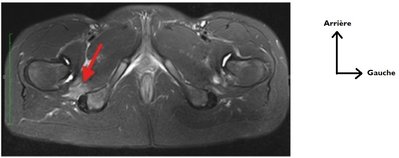

Page 15 on parle de la gouttiere inter trochantero ischiatique... je vois pas c’est ou